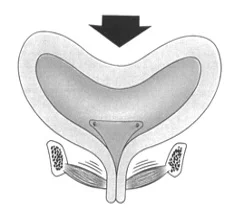

Stresová inkontinencia moču

Hyperaktívny mechúr